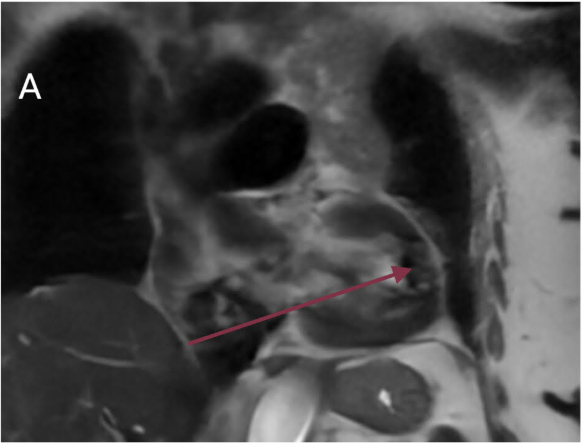

A 76-year-old woman with a significant smoking history presented with dizziness. Evaluation for syncope revealed normal orthostatic vitals and electrolytes. Electrocardiogram showed sinus bradycardia (heart rate 48 bpm) without QTc prolongation. Non-contrast CT of the head and CT angiography of the head and neck were unremarkable. Chest X-ray demonstrated left upper lobe atelectasis. Contrast-enhanced CT of the chest revealed bronchial obstruction in the left upper lobe and multiple pulmonary nodules in the right lung. Bronchoscopy identified a fungating mass obstructing the left upper lobe bronchus; biopsy confirmed adenocarcinoma. Transthoracic echocardiogram showed preserved left ventricular ejection fraction (60–65%), concentric hypertrophy, and grade I diastolic dysfunction. Cardiac MRI revealed a 3 cm mass along the basal anterior wall of the left ventricle with heterogeneous T2 signal intensity, consistent with myocardial metastasis. With a diagnosis of adenocarcinoma, the patient was advised to follow up as an outpatient for further oncologic management and advanced cardiac imaging.

This case highlights an incidental myocardial metastasis from lung adenocarcinoma in a patient presenting with bradycardia and dizziness, symptoms that may be related to cardiac involvement. While pericardial metastases are more common, myocardial infiltration is rare and often asymptomatic. Cardiac spread may occur via hematogenous, lymphatic, or transvenous routes and can present with arrhythmias, effusions, or hemodynamic compromise. Echocardiography is useful for initial evaluation, but cardiac MRI provides superior detail in assessing lesion characteristics and differentiating tumor from thrombus. Multimodal imaging plays a key role in identifying occult cardiac metastases that may impact clinical management.